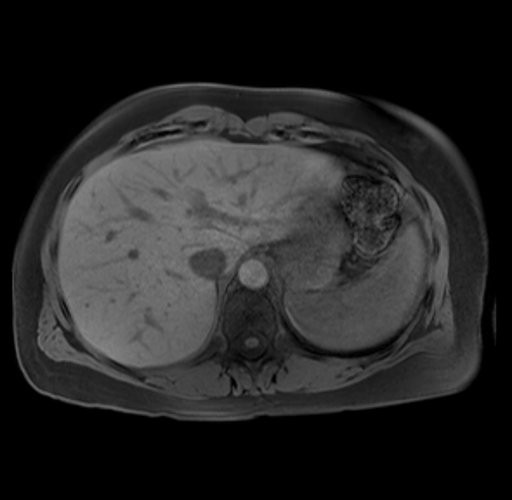

Imaging Analysis

Look through the patient's CT scan to identify any areas of concern for the necessary procedure.

Based on your CT findings, which issue(s) are present and would give reason for "planned slowing down moment(s)" in this case?

Considering a standard distal pancreatectomy procedure, what step(s) of the operation would you do differently in this case?